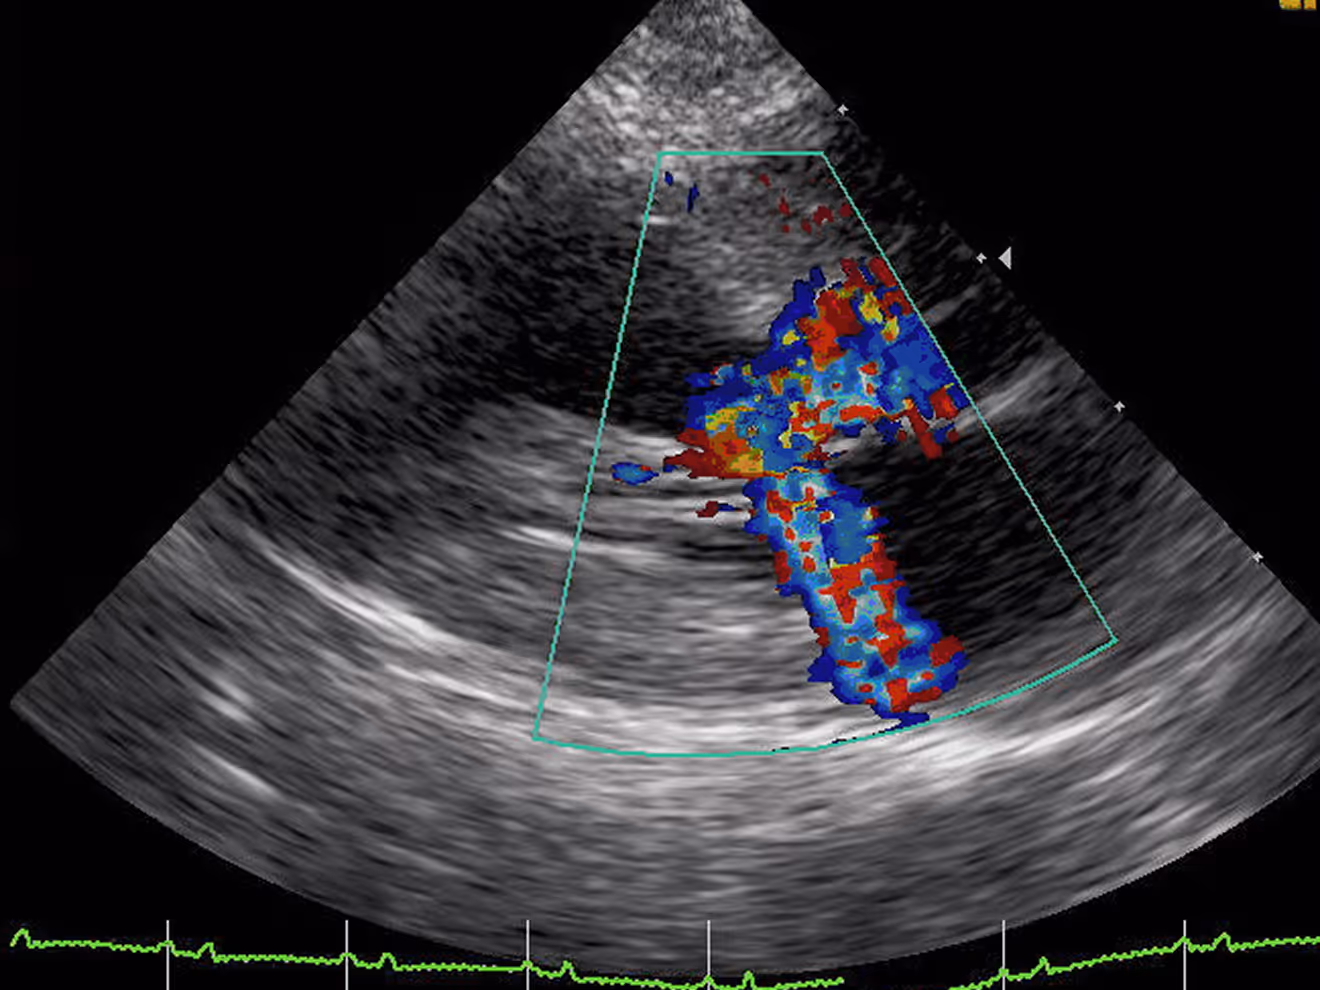

A cardiac workup may include echocardiography, electrocardiogram, digital radiographs, lab work, and blood pressure monitoring. These tests help identify the cause of heart murmurs, detect arrhythmias, assess fluid around the heart or lungs, and determine the stage of heart disease.

At Tandem Vet Somerville Clinic, we offer advanced cardiac diagnostics to help identify heart murmurs, evaluate clinical signs, and support breed-specific or pre-anesthetic screening. Our team uses tools such as echocardiography, ECG, digital radiographs, lab work, and blood pressure monitoring to clearly assess your pet’s heart health.